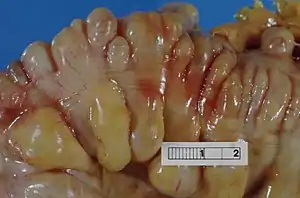

Meckel's diverticulum

Meckel's diverticulum Large bowel (sigmoid colon) showing multiple diverticula: the diverticula appear on either side of the longitudinal muscle bundle (taenium).